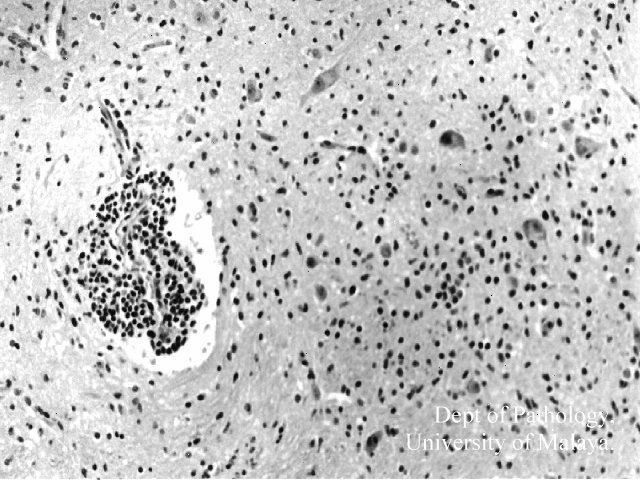

Figure 1 : Medulla: Perivascular inflammation and inflammatory cells in the parenchyma.

Figure 1 : Medulla: Perivascular inflammation and inflammatory cells in the parenchyma. Click on picture for larger picture.

The typical histopathological findings in the brainstem and spinal cord did not differ much from other types of viral encephalitides, and consisted of perivascular inflammation, microglial nodule formation, neuronal necrosis and phagocytosis, and mild meningitis. No neuronal inclusions were detected. The extent of the inflammation was remarkable in that it involved all levels of the spinal cord, medulla, tegmentum of the pons (spares the basis pontis) and much of the midbrain (spares the peduncles). In our cases there was no apparent involvement of the cerebellum, cerebrum or myocardium.